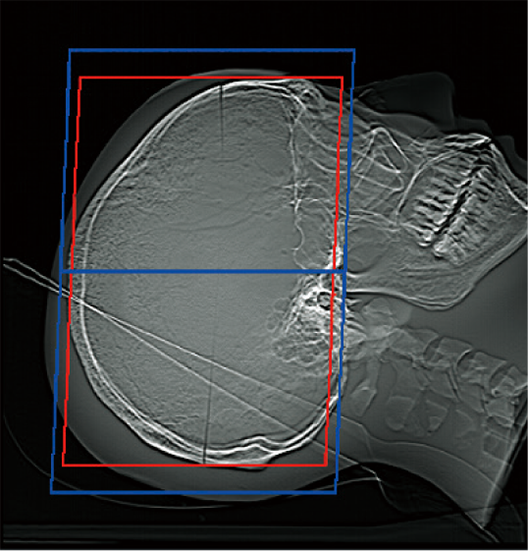

透過掃描定位圖影像,即可自動設定掃描範圍,有助於提升掃描位置的再現性與檢查效率,進而縮短整體檢查時間。

掃描範圍的邊界可依各醫療機構的作業習慣預先設定,實現符合需求的自訂化操作。操作者亦可隨時檢視與調整自動計算出的掃描範圍。*4

OM Line

SM Line

RB Line

Chest

紅色:自動設定位置

藍色:自動設定位置 + 設定邊界